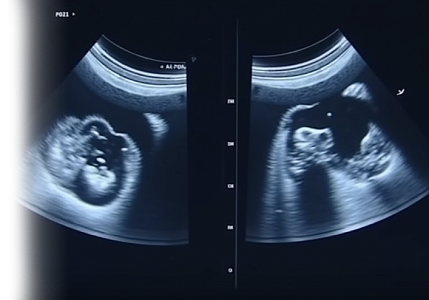

УЗИ на ранних сроках беременности

УЗИ на ранних сроках беременности (1 триместр) – ультразвуковой метод исследования, который позволяет не только подтвердить наличие беременности, но и предоставить ценную информацию о развитии плода и здоровья будущей мамы, выявить различные патологии и заболевания, что помогает своевременно принять меры по их лечению и предотвращению.

УЗИ-скрининг на 1 триместре беременности

УЗИ-скрининг 1 триместра беременности – ультразвуковой метод исследования для оценки здоровья плода и выявления возможных патологий.

УЗИ-скрининг на 2 триместре беременности

УЗИ-скрининг 2 триместра беременности – ультразвуковой метод исследования для оценки здоровья плода, его соответствия гестационному сроку и выявления возможных патологий.

УЗИ-скрининг на 3 триместре беременности

УЗИ-скрининг 3 триместра беременности – ультразвуковой метод исследования для оценки здоровья плода и выявления возможных патологий.